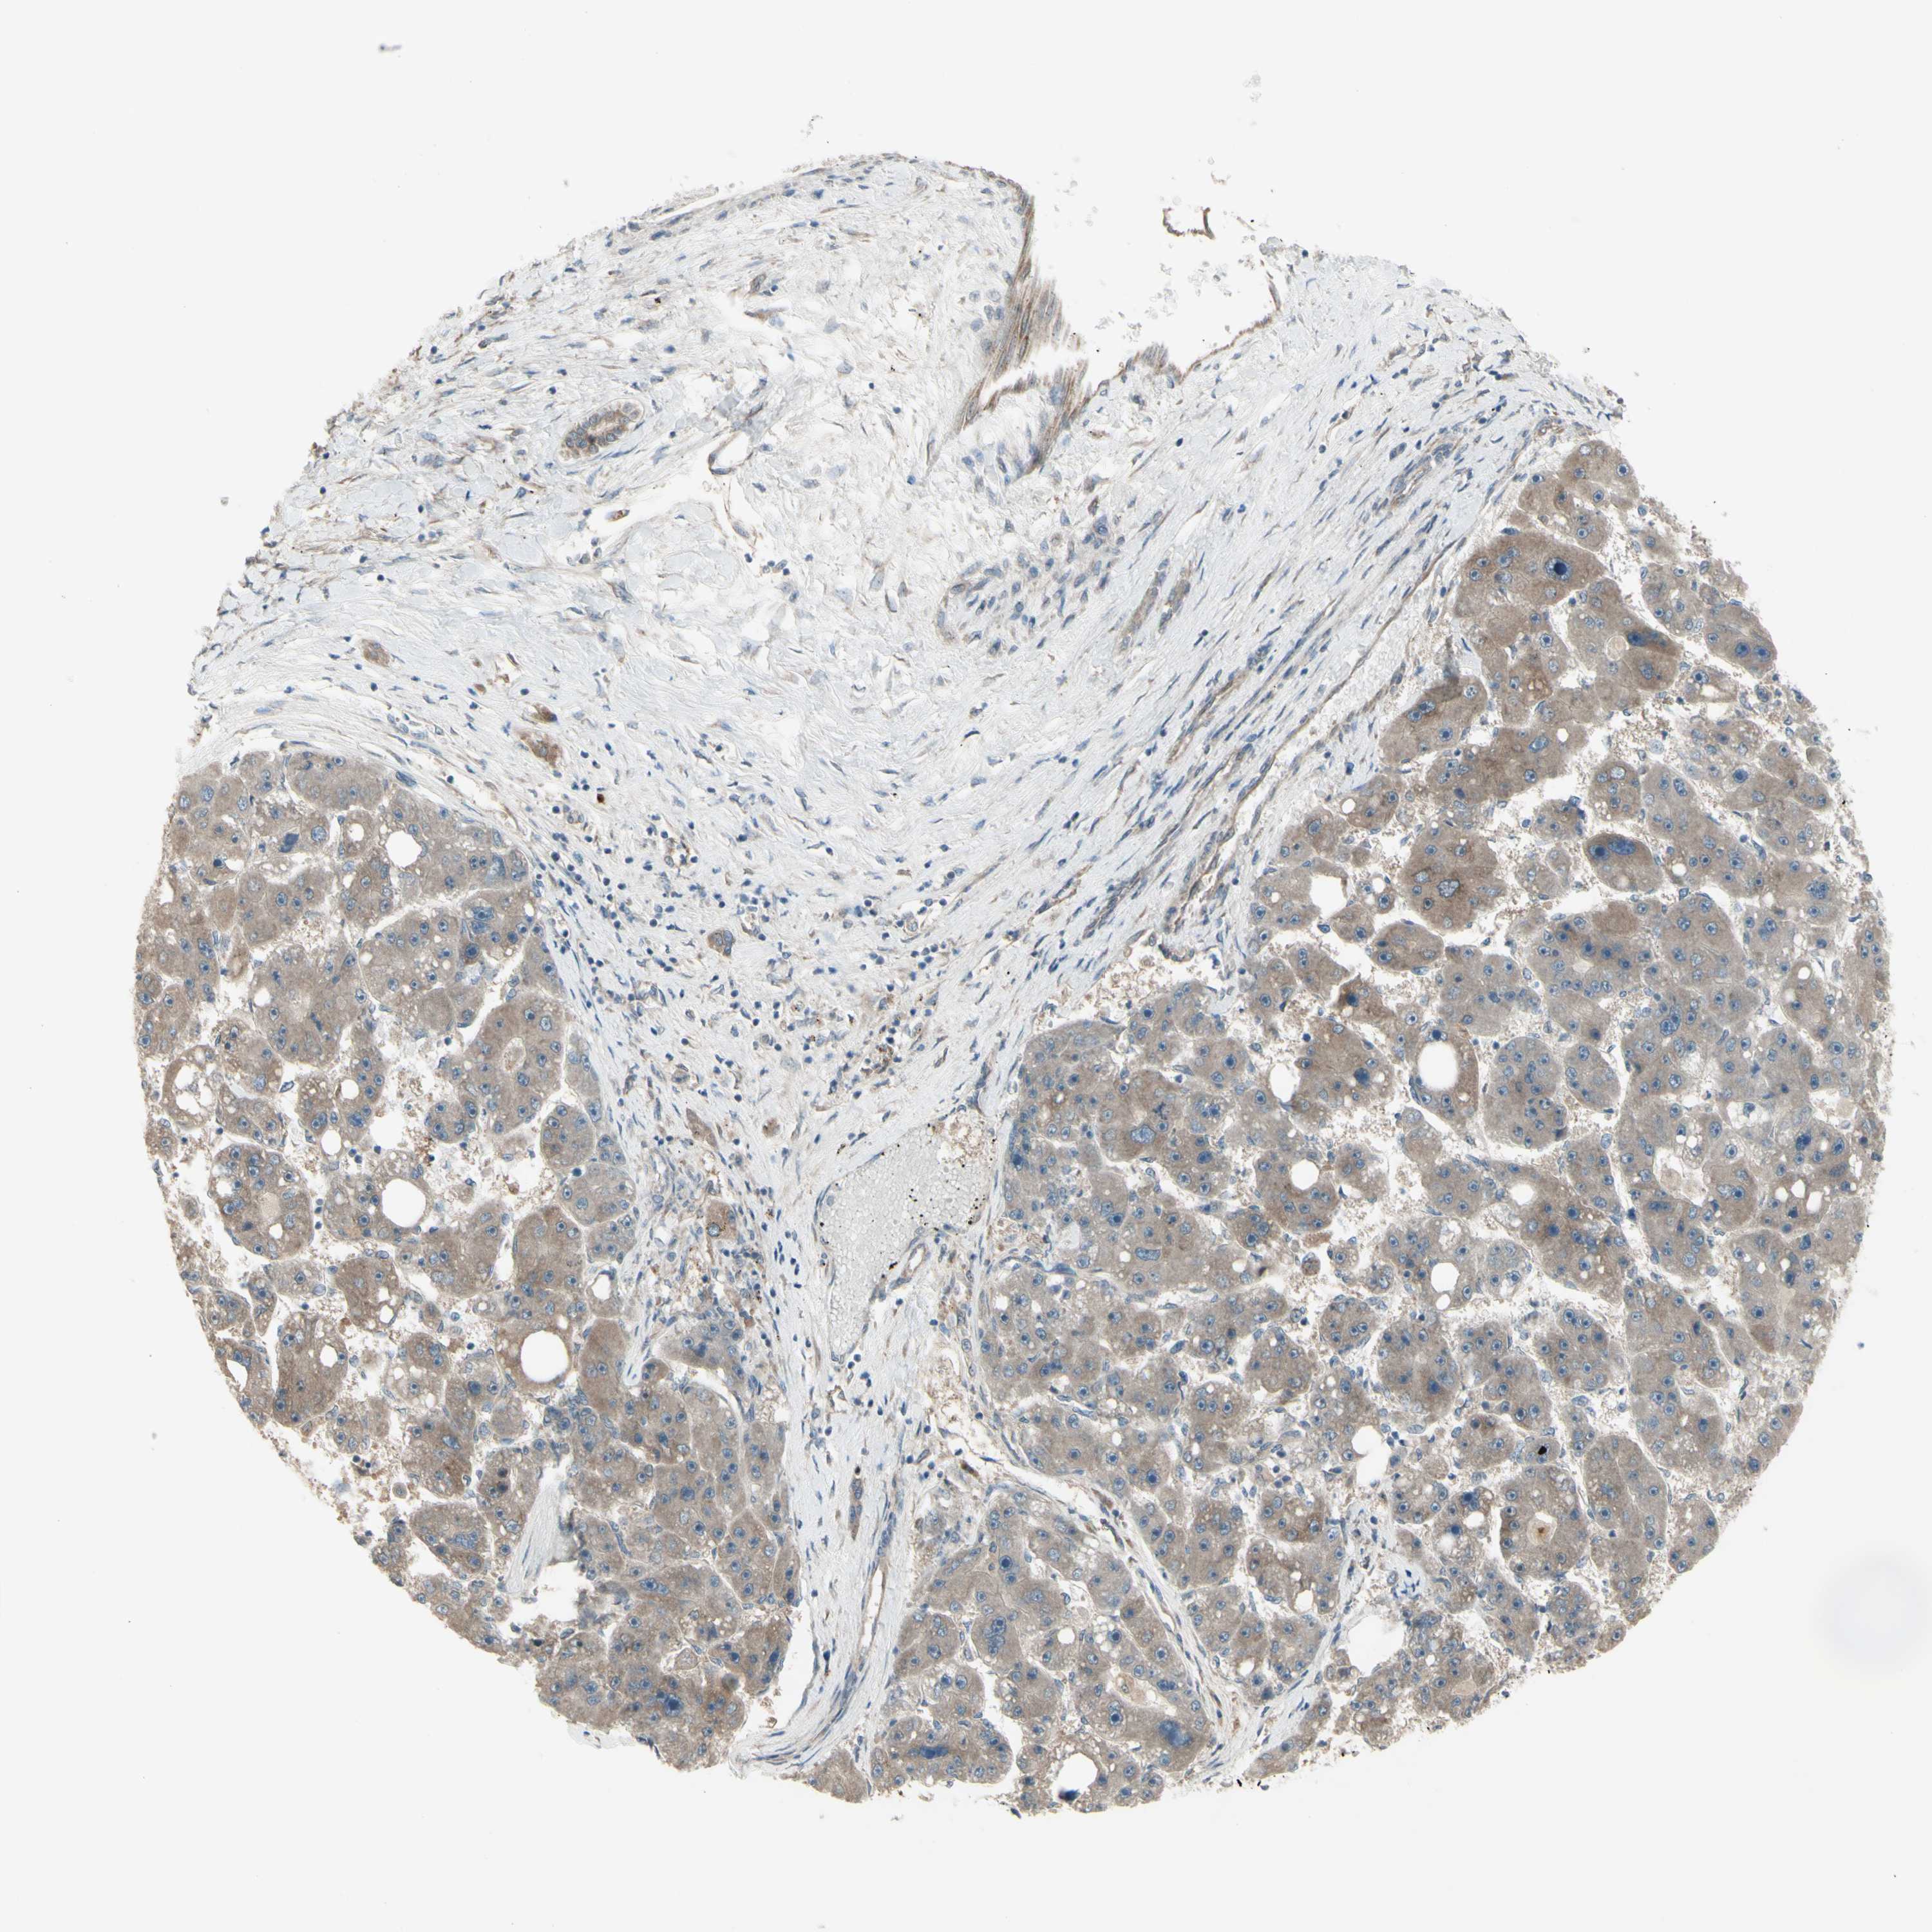

LIVER CANCER - Protein expressioni

A mouse-over function shows sample information and annotation data. Click on an image to view it in a full screen mode. Samples can be filtered based on level of antibody staining by selecting one or several of the following categories: high, medium, low and not detected. The assay and annotation is described here.

Note that samples used for immunohistochemistry by the Human Protein Atlas do not correspond to samples in the TCGA dataset.

Antibody stainingi

Antibody staining in the annotated cell types in the current human tissue is reported as not detected, low, medium, or high, based on conventional immunohistochemistry profiling in selected tissues. This score is based on the combination of the staining intensity and fraction of stained cells.

Each image is clickable and will lead to virtual microscopy that enables deeper exploration of all samples and also displays staining intensity scores, fraction scores and subcellular localization as well as patient and tissue information for each sample.

Antibody HPA010551

Staining

High

Medium

Low

Not detected

Intensity

Strong

Moderate

Weak

Negative

Quantity

>75%

75%-25%

<25%

None

Location

Nuclear

Cytoplasmic/membranous

Cytoplasmic/membranous,nuclear

Cholangiocarcinoma

Carcinoma, Hepatocellular, NOS